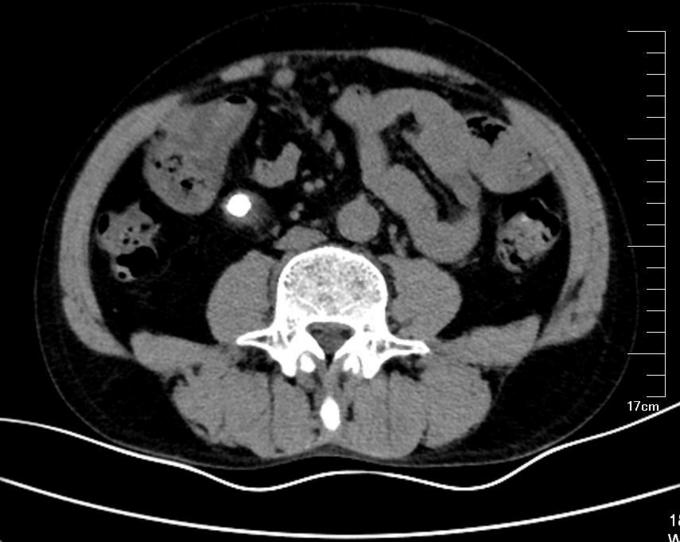

查体:右肾区明显压痛及叩击痛,左肾区无叩痛。右输尿管区轻微压痛,左输尿管区无压痛。膀胱区无明显隆起,未及包块,无压痛,叩诊无浊音。 辅查:我院泌尿系平扫CT+三维重建检查提示:右输尿管上段多发结石,右肾及输尿管重度积水,右肾萎缩。左肾盂略宽,结合临床。 我院肾图检查提示:1.右肾符合积水改变,功能重度受损。2.左肾GFR正常范围,功能正常。

诊断:右输尿管结石合并右肾重度积水。 治疗:给予右侧输尿管切开取石术。